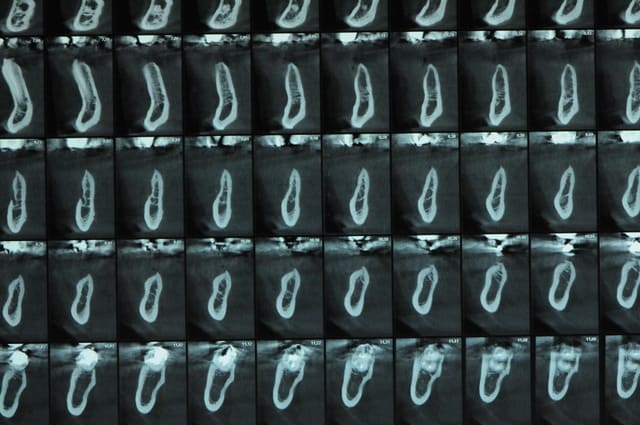

je post les coupes des que possible

J’ai une tranchée finale qui fait 8 à 9 mm moins 1 mm du trait de coupe donc il faudrait une triangulation pour le calcul mais je verrais les coupes scan une fois solidifié c’est + simple)

Merci pour la planification 3D, ça aide beaucoup à suivre ton cas. c'est quoi ton logiciel ?